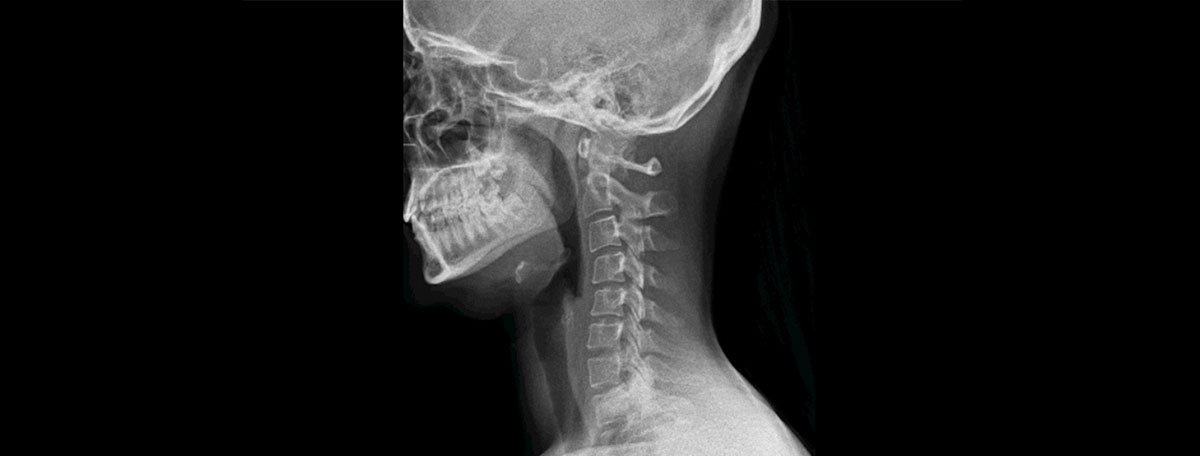

La radiología digital dinámica es una innovadora técnica de diagnóstico por imagen con la que se consiguen radiografías en movimiento en tiempo real.

La radiología digital dinámica o DDR (Dynamic Digital Radiography) utiliza rayos X para ver imágenes en movimiento del interior del cuerpo. Este efecto se consigue porque el equipo radiológico emite varios pulsos de energía sucesivos y rápidos durante unos segundos. Cuando se combinan todas las radiografías obtenidas, se percibe el movimiento de las estructuras corporales en tiempo real.

La novedad principal de la radiología digital dinámica es que durante 15 segundos emite 15 pulsos de radiación al segundo. Cuando se ven estas 225 diapositivas seguidas en forma de cine loop, se obtiene una radiografía en movimiento.